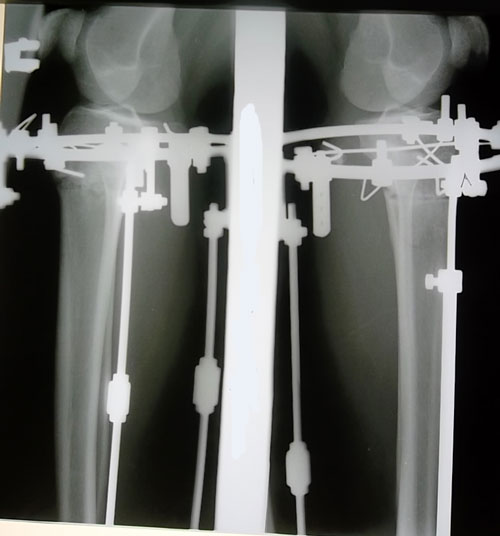

Рентгеновские снимки перед снятием аппаратов.

Вложения

SAM_6374.JPG

SAM_6373.JPG